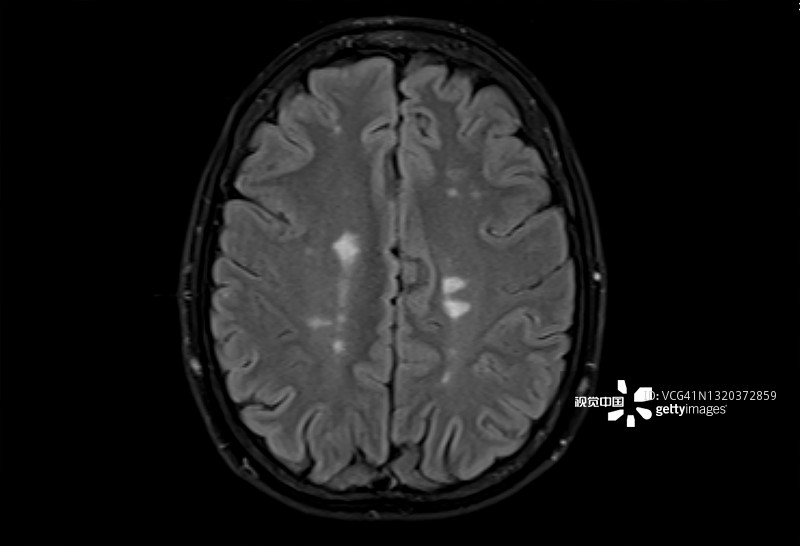

多发性硬化症 (MS):MS是一种中枢神经系统 (CNS) 的慢性自身免疫和炎症性疾病。MS与免疫系统介导的自身反应性T细胞和B细胞对神经元髓鞘的攻击有关,导致脱髓鞘并最终导致神经元丢失。由于中枢神经系统中神经变性和斑块的形成,MS患者会根据斑块的位置经历特定的神经功能障碍。例如,视神经中的斑块会导致视力丧失。